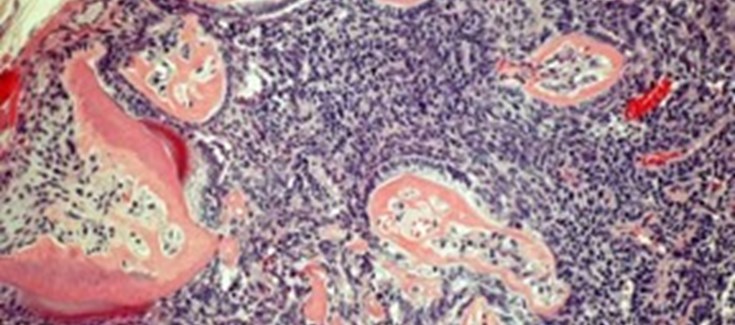

Masa tumoral con diferenciación en dentículos aberrantes.

Los tumores odontogénicos son un grupo de lesiones que se forman en la cavidad oral y que, como consecuencia de afectar a los tejidos responsables de la formación de dientes, se caracterizan por la formación de estructuras tumorales que diferencian como dientes. Este tipo de lesión tumoral es muy diverso, y el conocimiento de las bases moleculares responsables de la aparición de estos tumores dista mucho de ser completo.

IKKβ es una proteína con la capacidad de fosforilar, y de esta manera regular la actividad de numerosas proteínas diana, siendo por tanto un muy importante regulador de la fisiología celular. Entre las docenas de proteínas reguladas por IKKβ se encuentra la familia de factores transcripcionales NF-κB, cuya actividad desregulada se asocia en muchos casos a la formación de enfermedades inflamatorias y a tumores en distintos órganos y tejidos. En el presente trabajo se muestran los importantes cambios que suceden tanto en las poblaciones de células inflamatorias en el epitelio oral como en la expresión de microRNAs importantes en cáncer a consecuencia de la activación de IKKβ. Igualmente, se revela cómo la activación de IKKβ conduce, cuando está acompañada de la pérdida de proteínas supresoras de tumores (tales como p53, p16INK4a o p19ARF), a la aparición de tumores odontogénicos en aproximadamente el 25% de los individuos. Estos tumores, además, son capaces de formar metástasis en ganglios linfáticos y en pulmón.